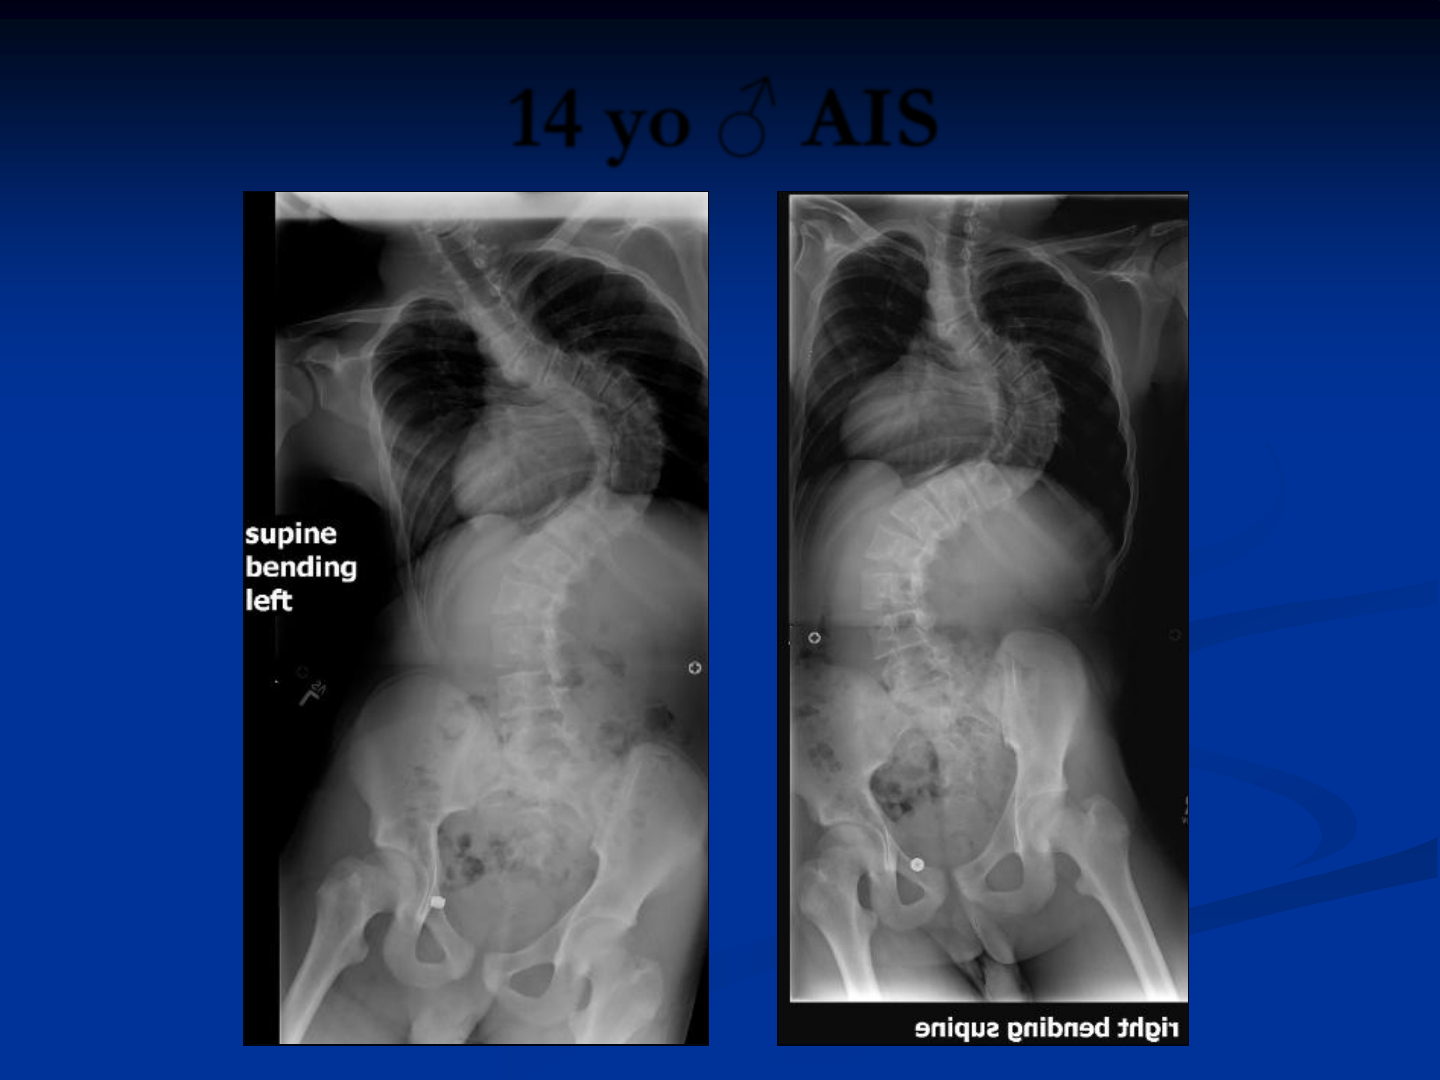

14 yo ♂ AIS

44

• Ant. Tscopic release

•Ponte osteotomies

•Rib head release

•Combination of

techniques for screw

insertion

45